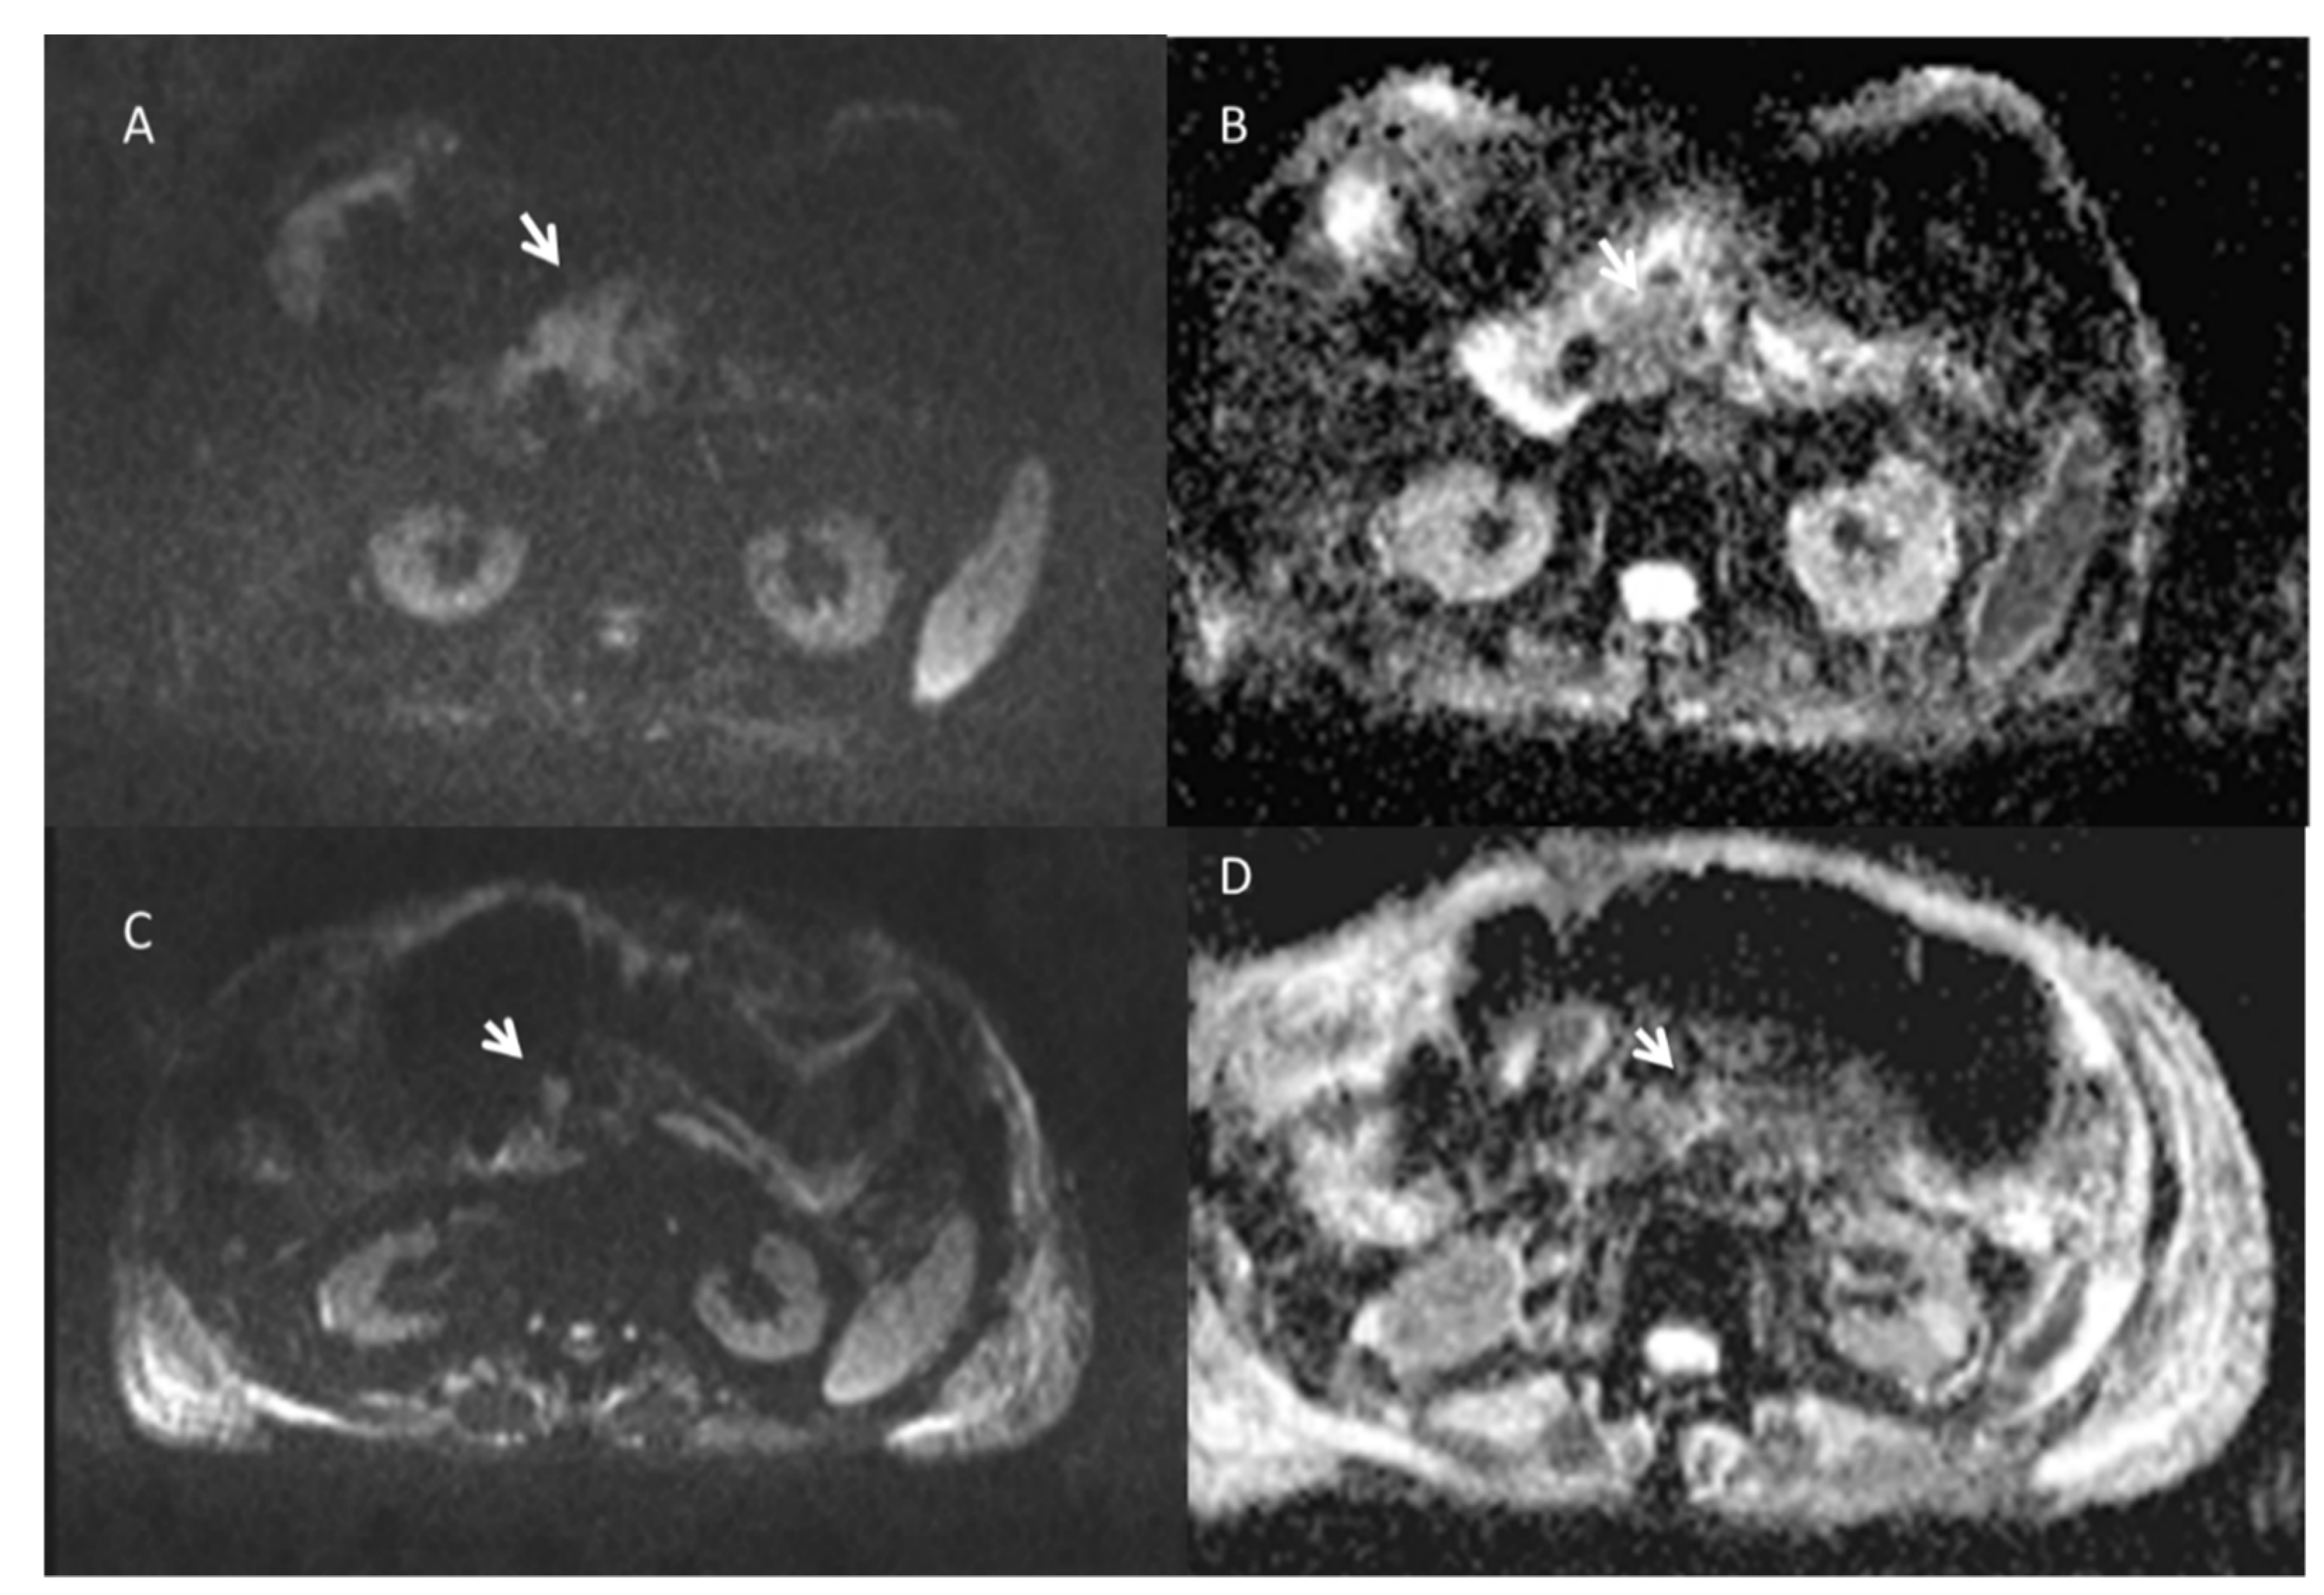

| The MD derived by DKI showed a significant increase between pre and post treatment and a significant statistically difference for percentage change between responders and not responders. | Post-IRE DW-MRI signal intensities notably decreased accompanied by a subsequent ADC increase. | ||||

| Magnetic Resonance Imaging | Persistent enhancement of the peritumoral liver parenchyma is observed within the IRE ablation zone. | On T1-weighted images, treated responsive lesions showed a nonhomogeneous signal, with a hyperintense central core and a hypointense peripheral rim. On T2-weighted sequences, the signal from the necrotic ablation zone was heterogeneously hypointense. The residual tumor tissue appeared as a peripheral portion that was hypointense on the T1-weighted images and hyperintense on the T2-weighted images. Three distinct layers on MRI in the irreversible electroporation ablation zone are visible: an inner layer of coagulative necrosis (hyperintense at T1- and T2-weighted imaging and non-enhancing), a middle layer of congestion and hemorrhage (hypointense at T1-weighted imaging, hyperintense at T2-weighted imaging, and progressively enhancing but hypointense at the hepatobiliary phase), and a peripheral layer of inflammation (hyperintense at the arterial phase but isointense at all other sequences). | On ceMRI spherical, oval or oblong area dependent to the number and type of electrodes used are visible. Treated lesion is heterogeneously or peripherally hyperintense on T1-weighted images and heterogeneous or hypointense on T2-weighted because of coagulative necrosis, hemorrhagic products and dehydration. The ablation zone is well demarcated, and no enhancement suggests a lack of viable tumor | [68,85,87,88,89,90,91] | |

| On ceMRI, no intravascular or perivascular enhancement was observed in responsive area. | On DWI, treated lesions showed restricted diffusion. | ||||